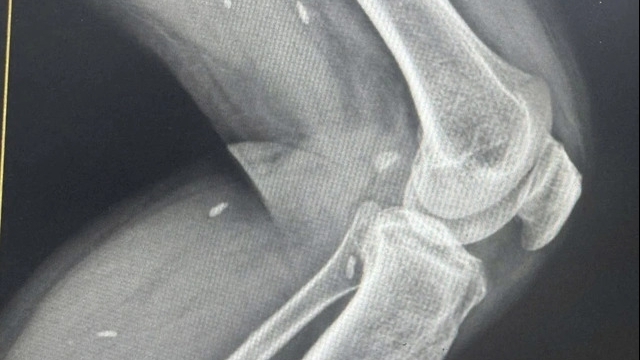

![]() |

| Các bác sĩ Bệnh viện HN Việt Đức đang ghép tim cho 1 bệnh nhân từ tạng hiến. Ảnh: BVCC |